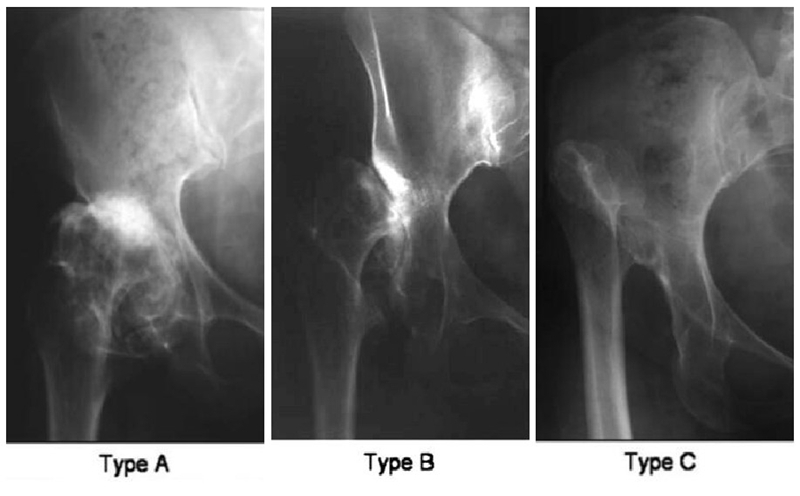

2、Hartofilakidis分型

Hartofilakidis于1996年提出成人DDH的简化分型方法。根据DDH病变程度的不同,使用三种类型分别对应髋关节发育不良、髋关节半脱位及髋关节脱位三种改变。

Ⅰ型:髋关节发育不良;

Ⅱ型:髋关节低位脱位;

Ⅲ型:髋关节高位脱位。